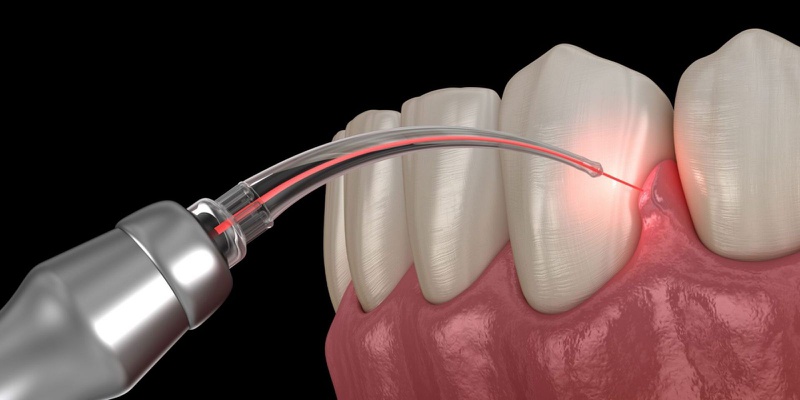

Cắt lợi bằng laser đang ngày càng phổ biến nhờ khả năng thẩm mỹ nướu nhanh chóng, giúp khắc phục cười hở lợi hoặc nướu thừa một